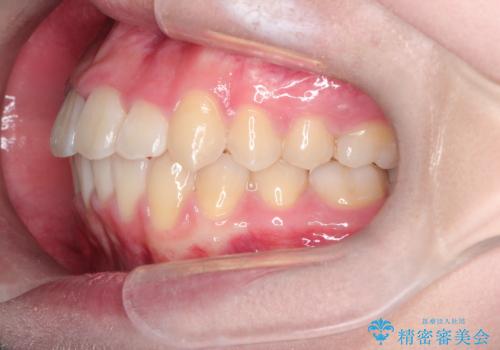

【インビザライン】前歯の凸凹を非抜歯で治療

- 前歯の凸凹を主訴の来院されました。

奥歯を後ろの方に移動させるために矯正用のアンカースクリューを使いながら治療をおこないました。

患者さんの都合により、マウスピースの装着時間が不足したため、途中からワイヤーにて治療を行いました。

インビザラインは20時間以上の装着は必要となるため、患者さんによってはワイヤーの方が向いていることがあります。